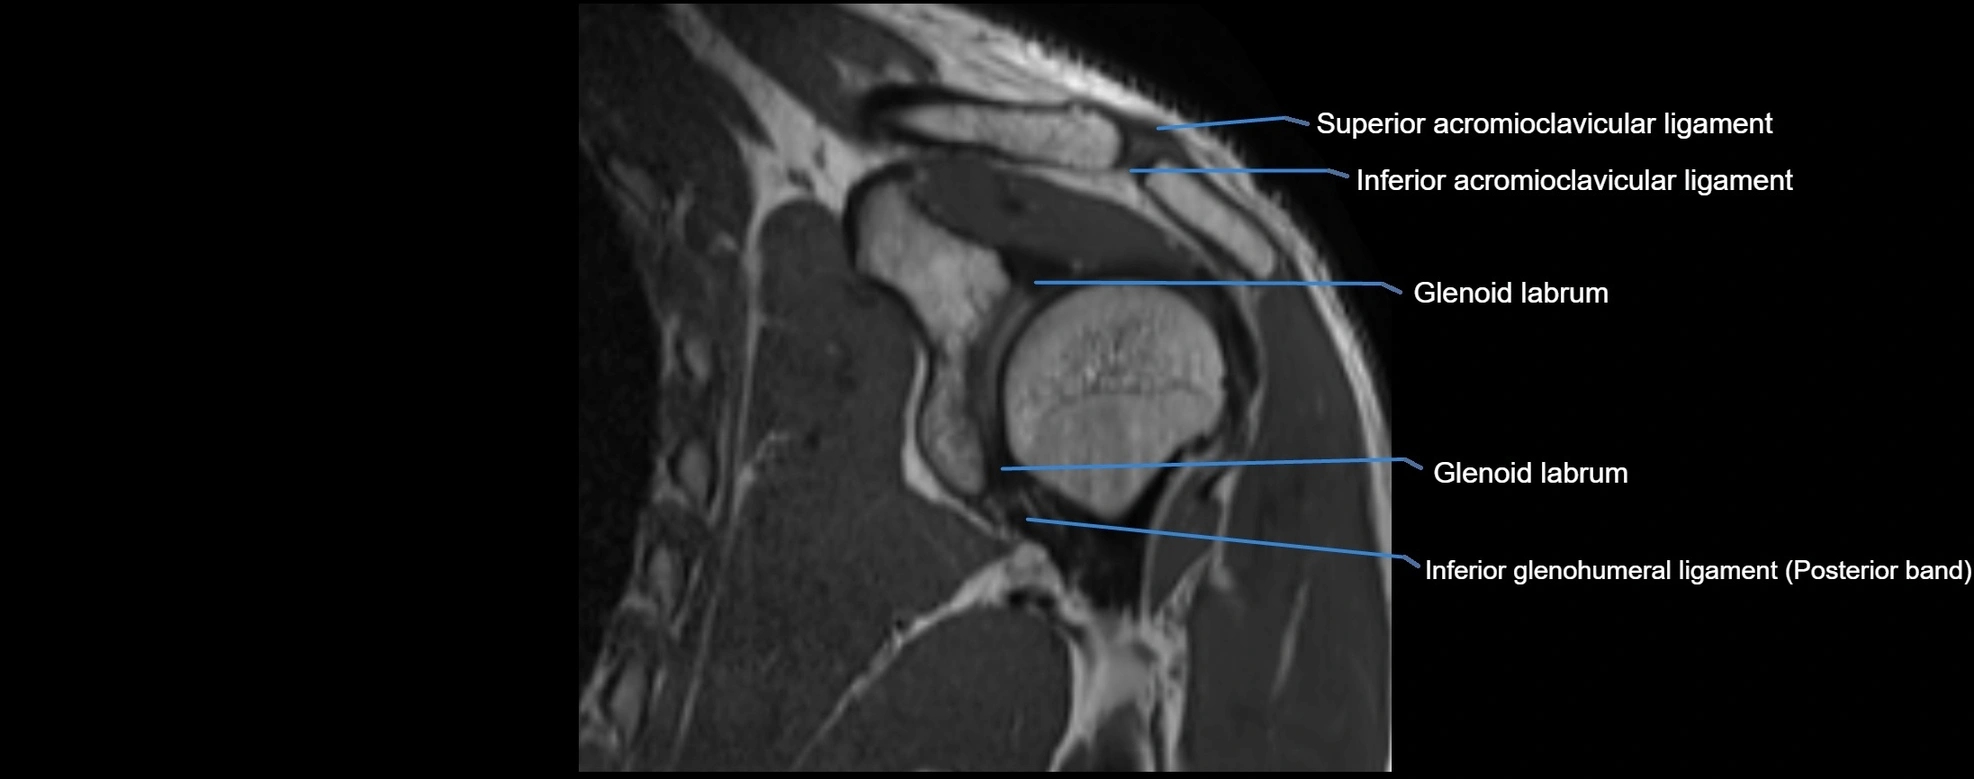

MRI Appearance

• T1-weighted images:

• Normal ligament: Low signal (dark linear band) spanning acromion to clavicle.

• Surrounding fat planes: Bright, delineating the ligament clearly.

• Marrow of clavicle and acromion: Bright due to fatty content.

• Tears: Discontinuity or irregular thickening with intermediate-to-bright signal.

• Chronic injury: Thinning, fraying, or irregular low-signal fibers with adjacent scarring.

• T2-weighted images:

• Normal ligament: Low signal, homogeneous.

• Partial tear or sprain: Focal hyperintensity or thickening.

• Complete tear: Discontinuity with fluid-bright gap between clavicle and acromion.

• Associated edema: Bright signal in distal clavicle or acromion marrow.

MRI images

image